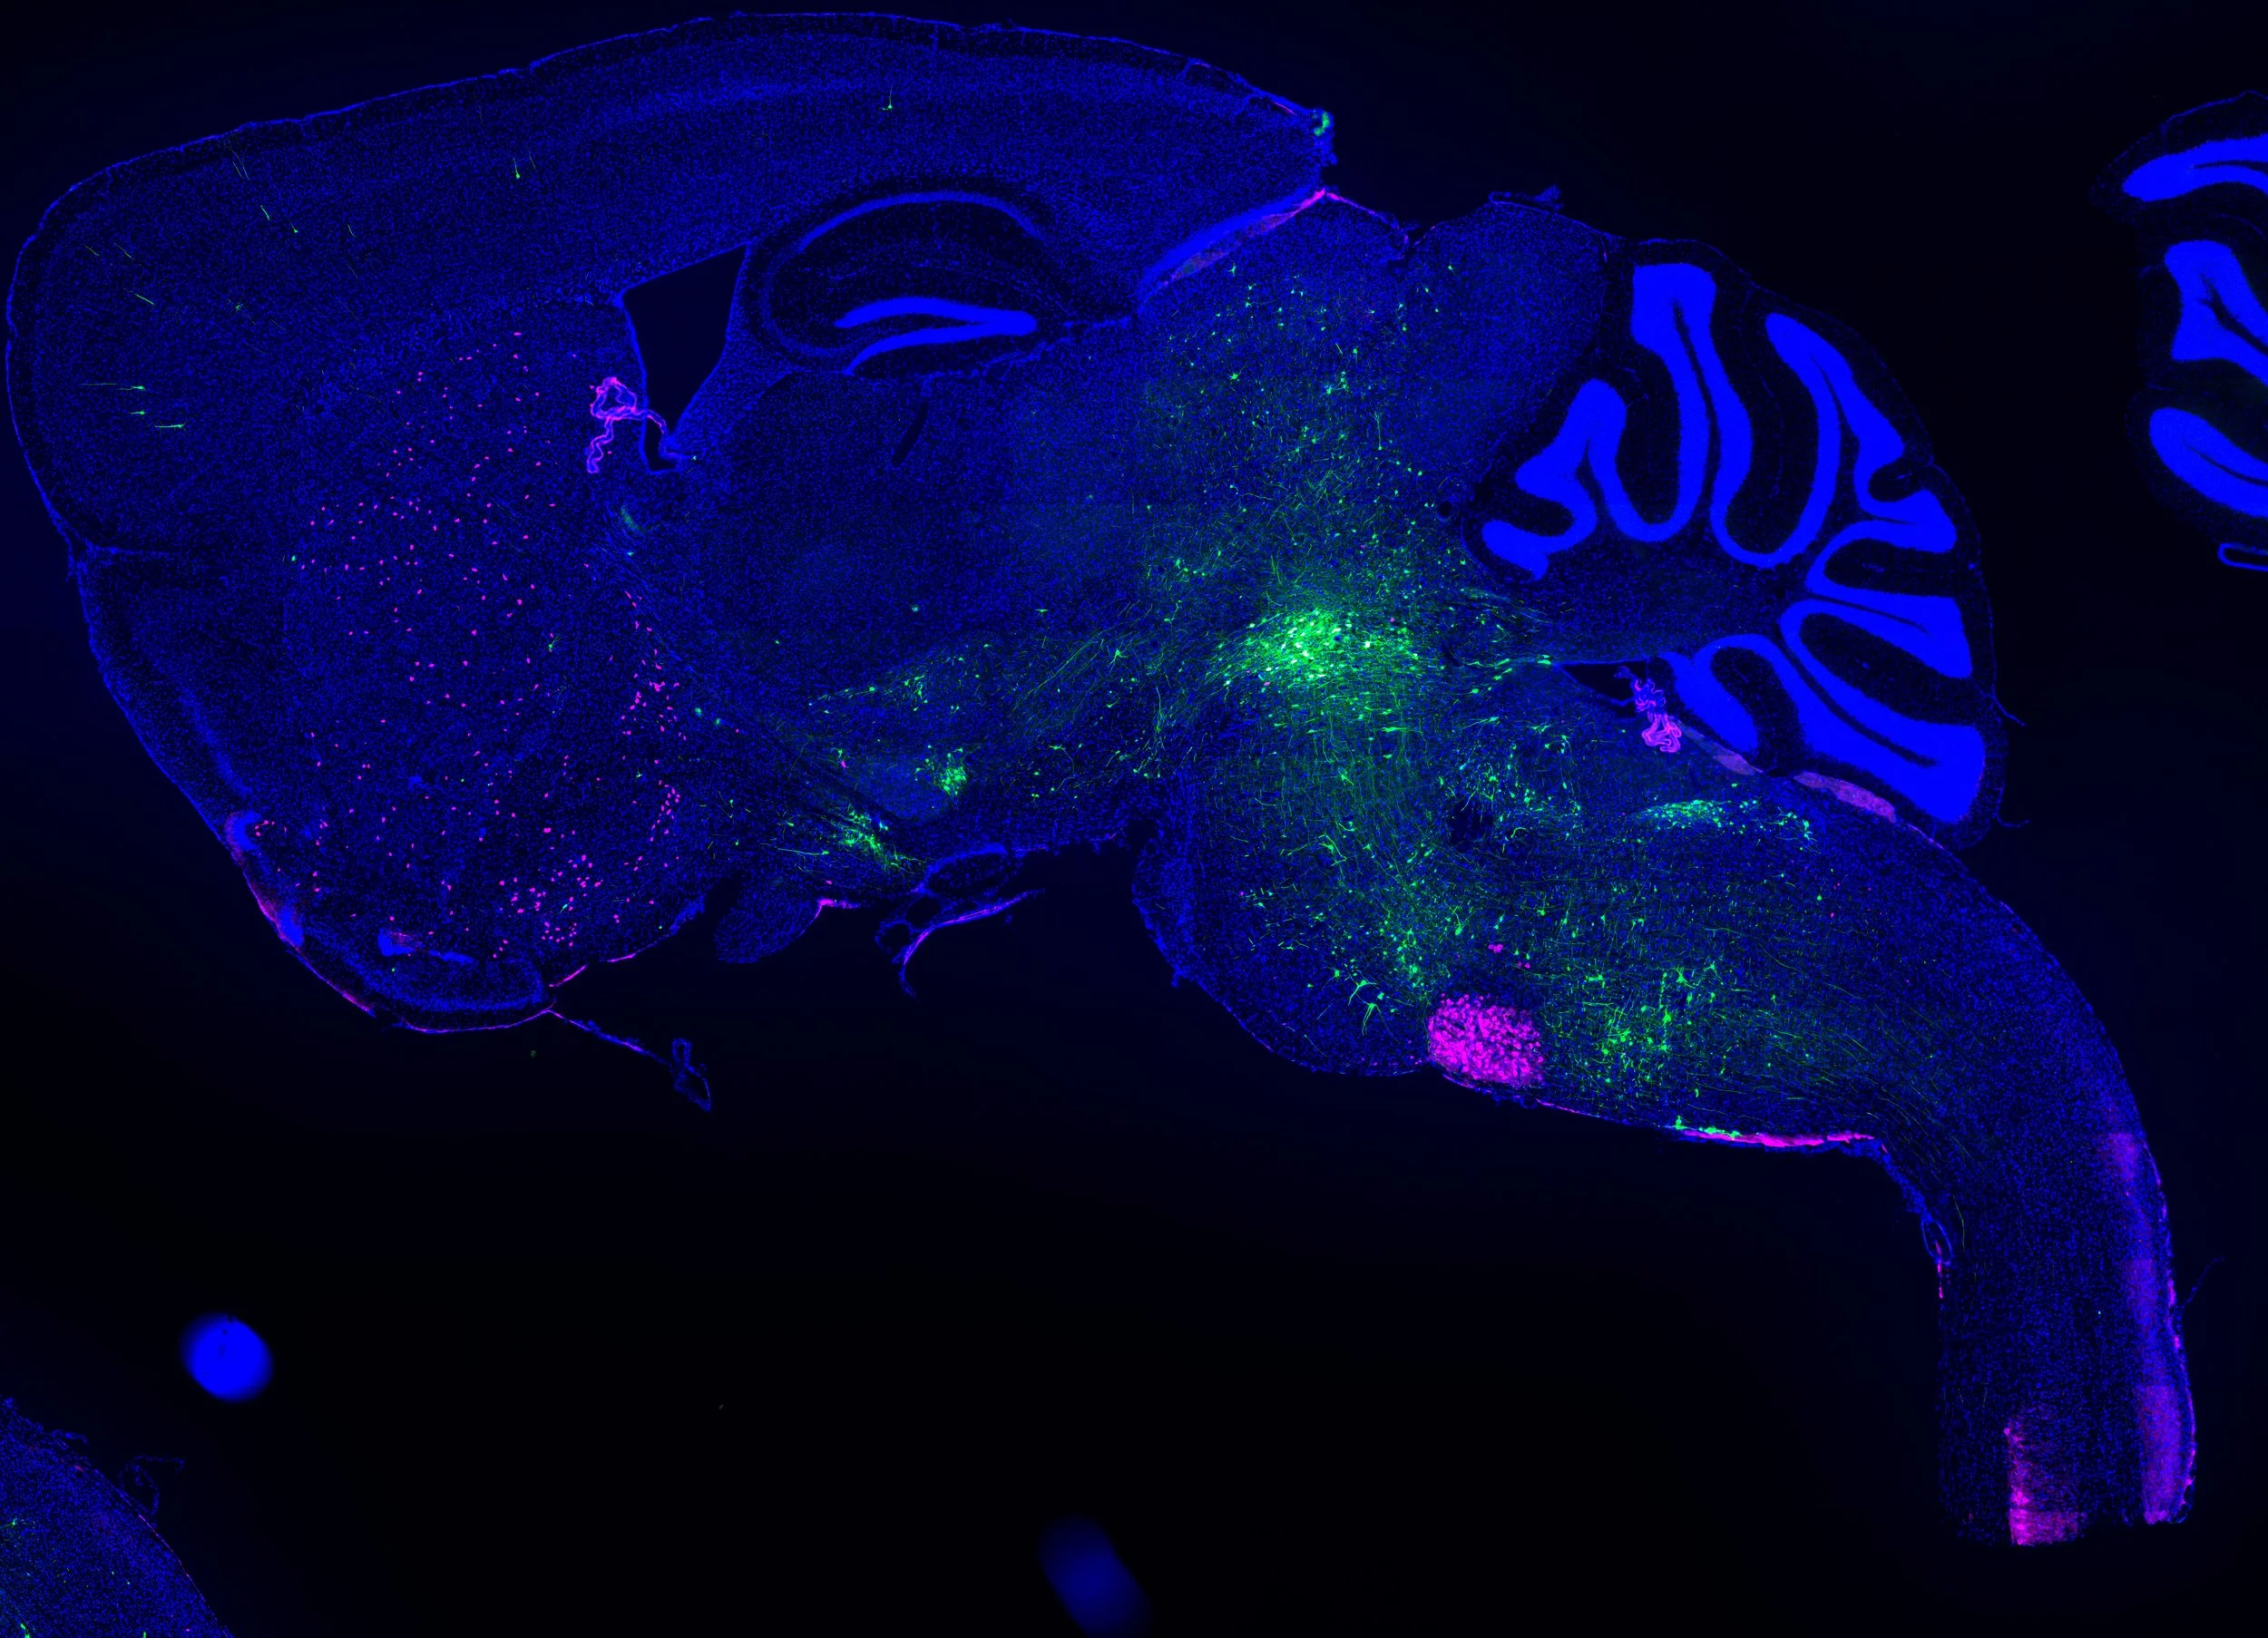

By combining state of the art neuroanatomical tracing with whole-brain pathology mapping techniques scientists at the CNP lab investigate how Parkinson’s disease pathology progresses in the brain. So far, this work has highlighted the importance of cellular vulnerability factors which render certain neurons more vulnerable to the disease process.

Initiating rabies virus tracing in the cholinergic population of the pedunculopontine nucleus.

Using rabies virus tracing to map neuronal connections.